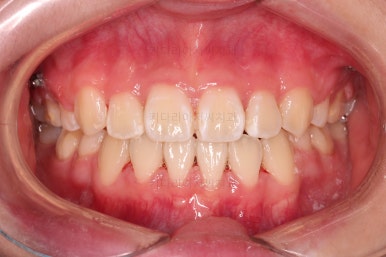

부산덧니교정 마무리를 한 모습인데요.

가지런한 모습 좋고, 교합이나 중앙선 등 매우 잘 맞네요.

전후를 비교해 볼게요.

치열, 교합, 악궁의 형태 매우 좋아졌어요.

다만 아직 어려서 카메라 사진을 찍을 때 어색해서 그런지 활짝 웃는 입술이 자연스럽진 않네요.

연습하면 충분히 좋아지고요.